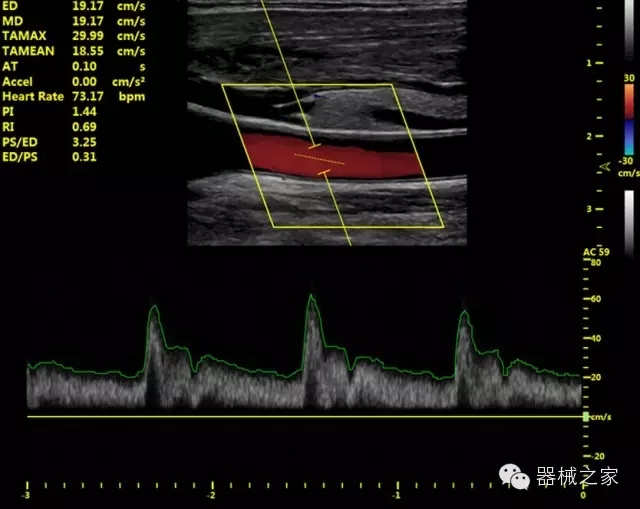

經(jīng)典產(chǎn)品:VINNO 6

臨床圖片賞析

Xcen探頭技術(shù)

·獨(dú)有的Xcen高頻18MHz探頭,使微小病灶的顯示成為現(xiàn)實(shí),為臨床提供了更廣泛的臨床應(yīng)用;

·Xcen超寬頻帶探頭技術(shù)比常規(guī)探頭頻寬提高了30%,具有更廣泛的臨床應(yīng)用,更高的頻率讓我們獲得了更好的細(xì)微分辨率和對(duì)比度的圖像;

肌骨理療

·智能感知組織特異性的VTissue技術(shù),結(jié)合特有高達(dá)22MHzXcen線陣探頭, 以及獨(dú)有敏感的RF射頻血流提供了優(yōu)異臨床圖像;